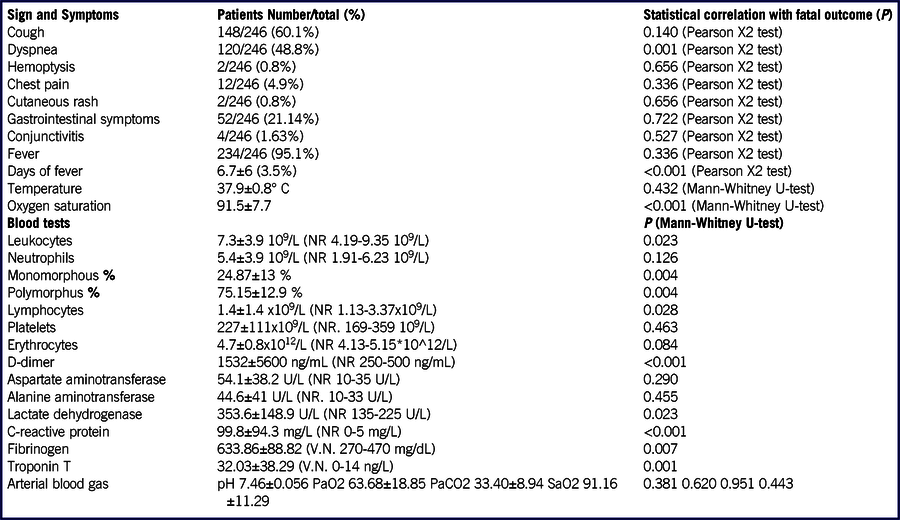

According to our exclusion criteria, 246 patients were enrolled. Most patients were men (170/246; 69%), with a mean age of 63 y; 154/246 patients (62%) have at least 1 chronic disease (Table 1). Upon admission, most patients had fever (234/246; 95%) and cough (148/246; 60%); C-reactive protein levels were increased in the 216/246 (88%) of patients (Table 2).

TABLE 2 Patients Signs, Symptoms, and Laboratory Tests and Their Correlation With Fatal Outcome

Abbreviation: NR, normal range.

Analyzing symptoms upon admission, only dyspnea correlated with mortality (P = 0.001); fever did not correlate (P = 0.336), but the days of fever did (P < 0.001).

Among blood tests, C-reactive protein, D-dimer, and fibrinogen were significantly correlated with the outcome (P = 0.001).

In our retrospective study, we observed that the fatal outcome had a significant correlation with sex, age, various comorbidities, the assumption of ACEi, and days of hospitalization (< 0.001). The only symptom upon admission with a significant correlation was dyspnea, whereas, among blood tests, mainly troponin T, C-reactive protein, D-dimer, and fibrinogen significantly correlated with the outcome. Regarding radiological variables, consolidation, peripheral GGO, pleural effusion, and the severity score showed a significant correlation.